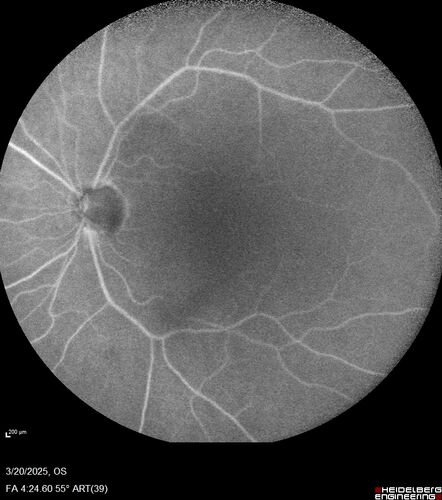

Paclitaxel induced cystoid macular edema - reversed when chemo stopped

74 year old retired physician  About 2-3 weeks ago there was gradual vision loss in the right eye. The patient was seen by an ophthalmologist who saw macular swelling and injected vabysmo. He has been on chemotherapy (Carbiplatin and Carboxytaxol for 2 cancers - advanced prostrate diagnosed 2019 - has had brain surgery AND squamous lung cancers treated with radiation)

VA OD: Dcc20/125+1

VA OS: Dcc20/125-2

TP: OD:12 OS:15